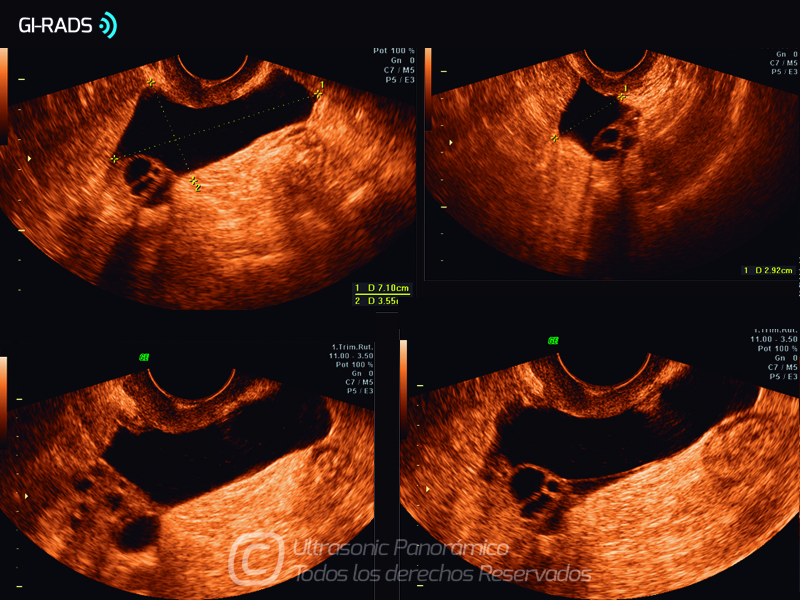

Patologías Benignas – Pseudoquiste de Inclusión Peritoneal

• Patologías Benignas – Pseudoquiste de Inclusión Peritoneal